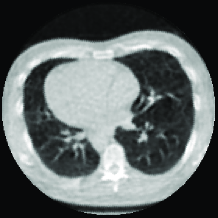

Reconstructions of a chest CT scan from a hospital patient using FBP from 1200 projections and the proposed method from 256 projections is shown in Figure 10.

It is evident that the image reconstructed with the proposed method has almost the same quality as FBP, which has about 5 times more projections,

i.e. 5 times the radiation dose. While the image from the proposed method is a little blurry compared to FBP reconstructed image, but all the details are preserved.